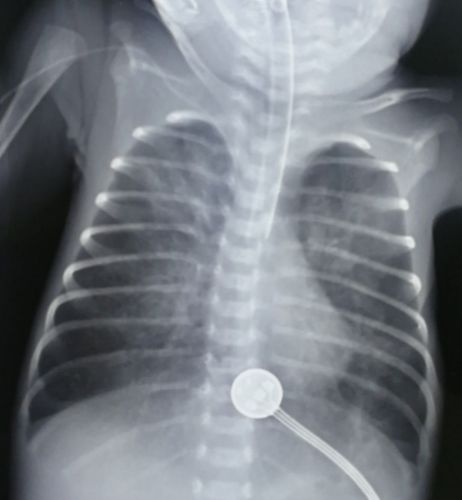

肺不张胸片典型图片

肺不张胸片典型图片,肺不张胸片表现图片

灌洗后当天复查胸片肺不张消失

肺不张胸片表现图片

肺不张x线图片

肺不张胸片表现

肺不张胸片

肺不张图片

肺不张x线表现图片

肺不张x线表现

肺不张x线